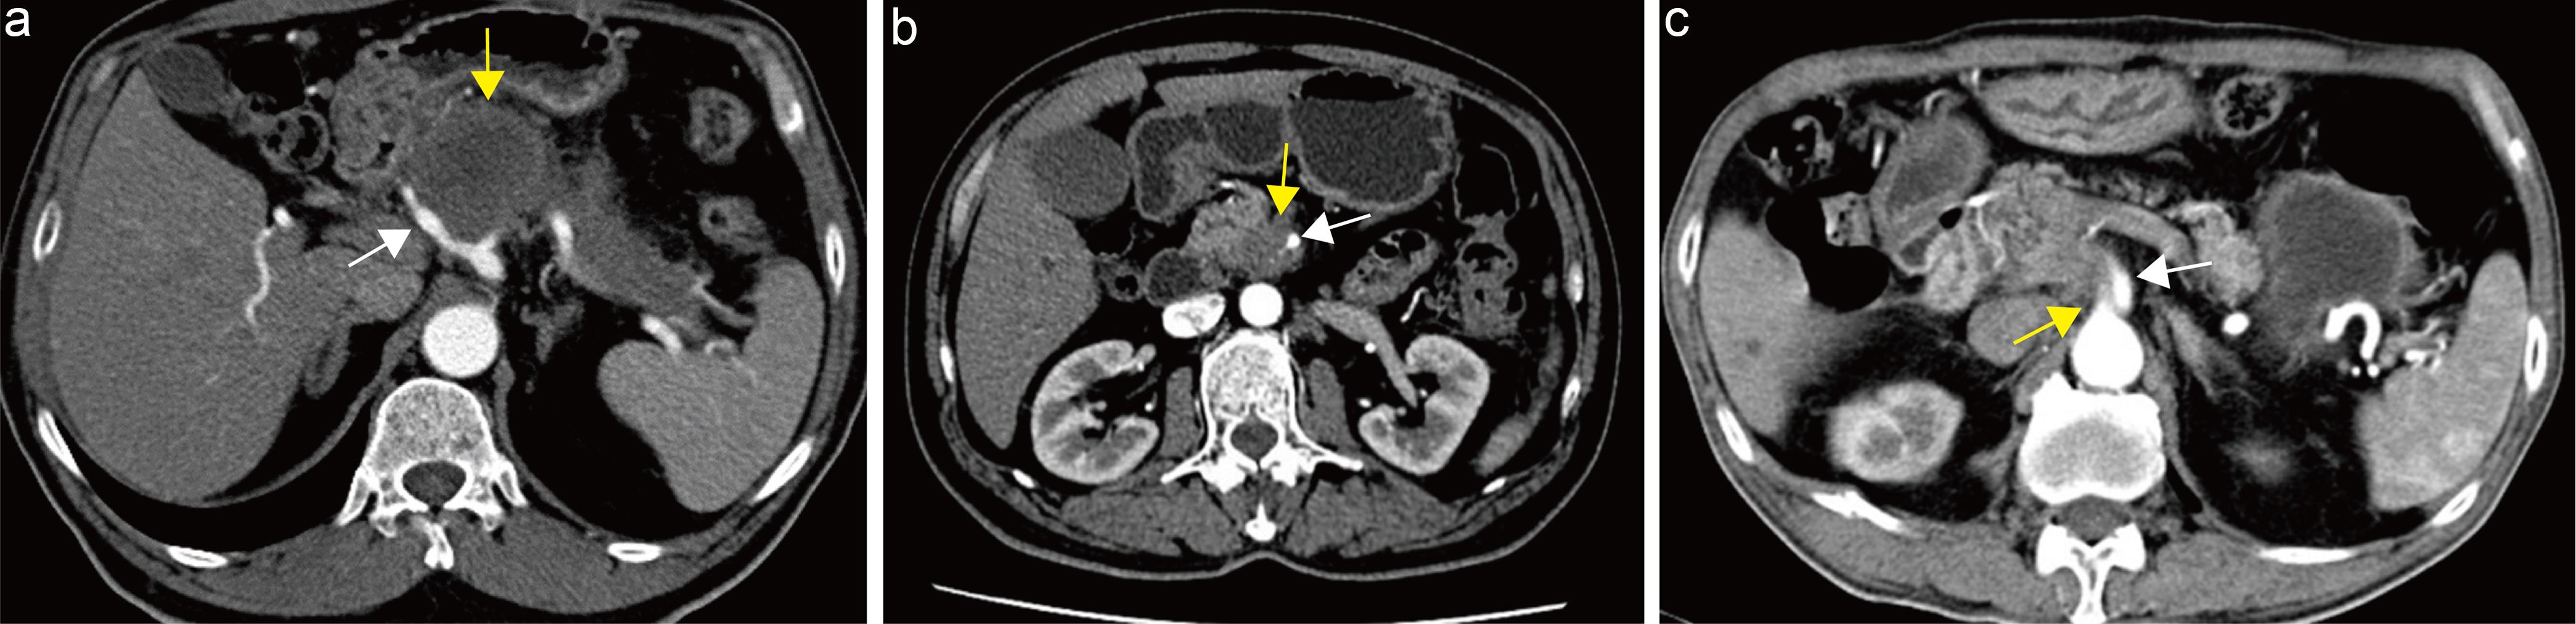

Explanation: Approximately 13–23% of pancreatic cancer patients are found intraoperatively to have hepatic or peritoneal metastases, rendering the tumor unresectable.130 Although multiphasic helical CT with volumetric scanning has improved detection rates of metastatic lesions, contrast-enhanced CT sensitivity for hepatic metastases remains suboptimal (38–76%).131 MRI with DWI demonstrates high sensitivity (86–97%) for detecting focal hepatic lesions, including subcentimeter metastases (sensitivity 60–91%).132–134 Meta-analyses indicate that MRI outperforms CT in overall diagnostic accuracy for hepatic metastases in pancreatic cancer, with pooled sensitivity higher for MRI than CT (85% vs. 75%), while pooled specificity is comparable (98% vs. 94%).135 Another meta-analysis similarly found comparable specificity between CT and MRI (94% vs. 96%) but superior sensitivity for MRI (83% vs. 45%) in diagnosing hepatic metastases.136 Peritoneal metastases from pancreatic cancer typically manifest as miliary nodules on the omentum and mesentery, irregular peritoneal thickening, and small-volume ascites, all suggestive of peritoneal carcinomatosis or implantation (Fig. 12).137 CT sensitivity for peritoneal metastases depends on lesion size; Archer et al.138 reported sensitivity of only 25% for lesions <0.5 cm, increasing to 90% for lesions >5 cm. MRI, including DWI sequences, is a sensitive imaging modality for detecting peritoneal metastases.139 Studies suggest that combining high b-value (b = 800 s/mm2) DWI with conventional MRI improves preoperative detection sensitivity (from 0.58 to 0.85) and accuracy (from 0.67 to 0.85) for peritoneal tumors compared to conventional MRI alone.140

Evaluation of hepatic and distant metastases in pancreatic cancer.

Fig. 12  Evaluation of hepatic and distant metastases in pancreatic cancer.

a, b Same patient. (a) Axial portal venous–phase T1-weighted MRI showing a hypointense mass in the pancreatic body and tail (white arrow). (b) Axial portal venous–phase T1-weighted MRI showing multiple ring-enhancing lesions in the liver (yellow arrows), consistent with hepatic metastases. c, d Same patient. (c) Axial portal venous–phase CT showing a hypodense mass in the pancreatic body and tail (white arrow). (d) Axial portal venous–phase CT showing nodular changes of the omentum (yellow arrow), consistent with omental metastases. CT, computed tomography; MRI, magnetic resonance imaging.